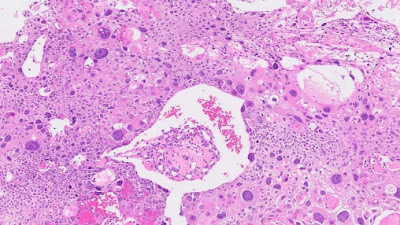

Pathologic Staging,  Histopathology and Cervical Cancer Screening

In cases treated by surgical procedures, the pathologist’s findings in the removed tissues can be t… Read More » Pathologic Staging, Histopathology and Cervical Cancer Screening